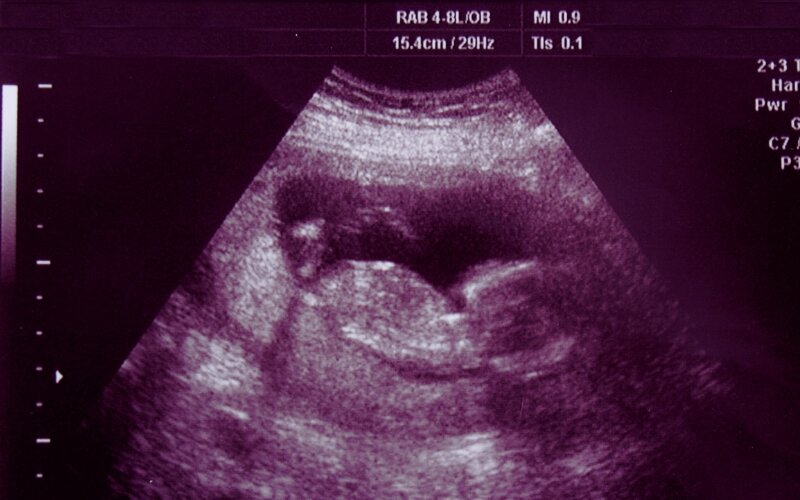

غربالگری معمولا در سه ماهه اول و دوم بارداری انجام میشود و میتواند شامل آزمایش خون، سونوگرافی و در موارد خاص، آزمایشهای تشخیصی دقیقتر مانند آمنیوسنتز باشد. هدف اصلی از این بررسیها، شناسایی خطر ابتلا به بیماریهایی مانند سندروم داون، تریزومی ۱۸ یا ناهنجاریهای ساختاری در جنین است.

سونوگرافی NT

هدف این مرحله، بررسی احتمال وجود سندرم داون (تریزومی ۲۱)، تریزومی ۱۳ و ۱۸ است. در صورت بالا بودن ریسک، پزشک ممکن است آزمایشهای تشخیصی دقیقتری را توصیه کند.